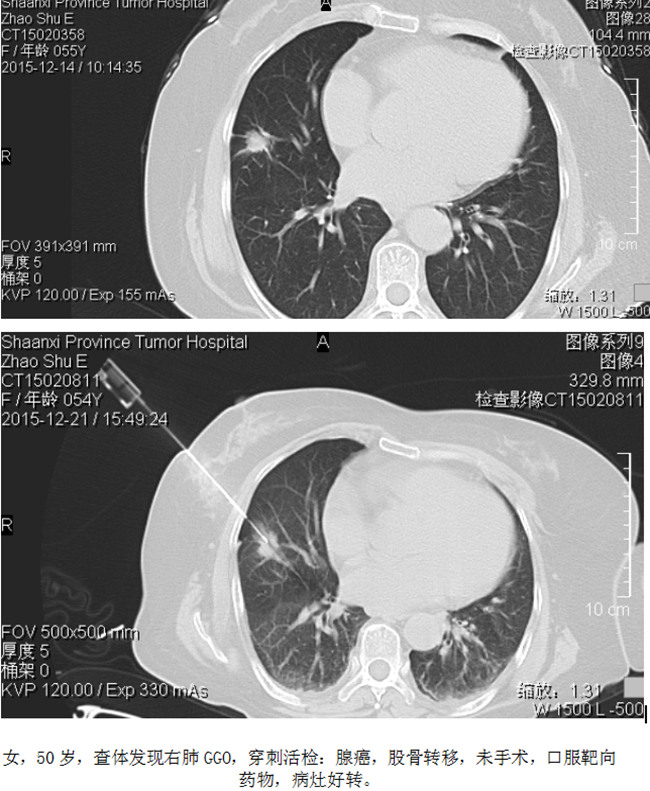

5、CT定位穿刺活检

这是一个具有争议性话题,有人不建议,认为并发症多,阳性率率低。我们认为,要看病灶的大小,部位,具体的病灶具体对待,不能一概而论。CT定位穿刺活检可以确定病灶的良恶性,对指导治疗是很有益的。

穿刺案例: